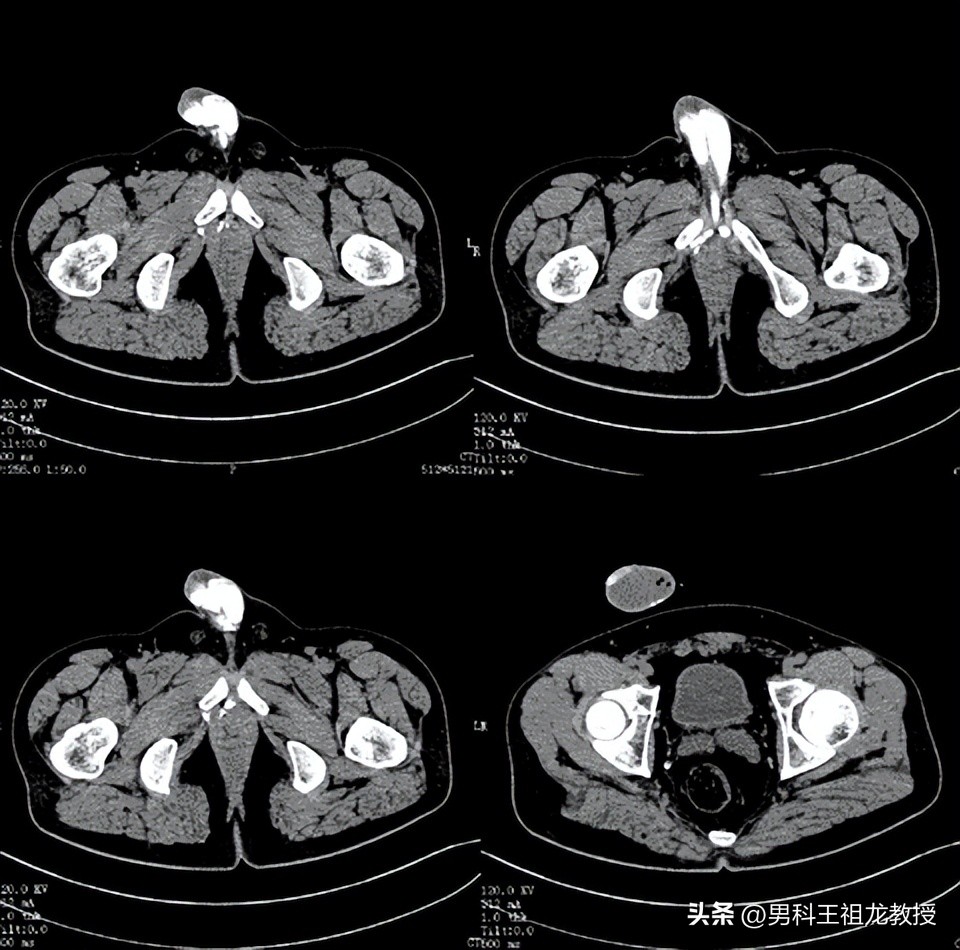

影像表现可见 :阴茎右侧海绵体较左侧充盈差,右侧海绵体脚静脉、阴部内静脉及右侧髂内静脉显影。阴茎远端背深静脉显影显著。

造影剂增强计算机断层扫面成像

王祖龙主任仔细阅片后,告知患者其明确诊断为 静脉性勃起功能障碍 ,在阴茎背深静脉及阴茎右侧海绵体脚静脉存在两处静脉漏,建议患者择期手术治疗 。